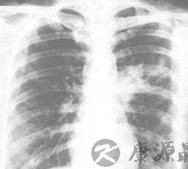

X线胸片胸部X线检查诊断间质性肺疾病的常用方法之一。早期肺泡炎显示双下肺野模糊阴影,密度增高如磨砂玻璃样,由于早期临床症状不明显,患者很少就诊,易被忽略,病情进一步进展,肺野内出现网状阴影甚至网状结节状阴影,结节1~5mm 大小不等。晚期有大小不等的囊状改变,呈蜂窝肺,肺体积缩小,膈肌上抬,叶间裂移位,发展至晚期则诊断较易,但已失去早期诊断的意义。约有30%患者肺活检证实为间质性肺纤维化,但胸部X 线检查却正常,因此X 线检查对肺泡炎不够敏感,且缺乏特异性。肺部CT 或高分辨CT:对肺组织和间质更能细致显示其形态结构变化,对早期肺纤维化以及蜂窝肺的确立很有价值,CT 影像的特点包括结节影,支气管血管壁不规则影,线状影和肺野的浓度等四种影像,结节可出现在小叶的中心、胸膜、静脉周围、细静脉和支气管血管壁的不规则影处。同样支气管血管壁不规则出现于小叶中心,支气管动脉和静脉及细静脉的周围。高分辨CT 影像对间质性肺病的诊断明显优于普通X 线胸片,对于早期的肺纤维化以及蜂窝肺的确立很有价值。尤其CT 影像在判定常以周边病变为主的ILD 具有独特的诊断价值。